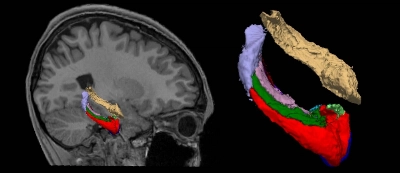

The hippocampus is a part of the brain that controls memory, learning and emotions. Stressful life events such as disasters and terrorist attacks are known to lead to post-traumatic stress disorder and result in its shrinkage.

JAPAN / Science & Health

Feb 9, 2024

Tokyo teens were less stressed during first COVID emergency: study

Increases in the volume of the hippocampus in their brains suggest reduced stress, according to research conducted by the University of Tokyo.